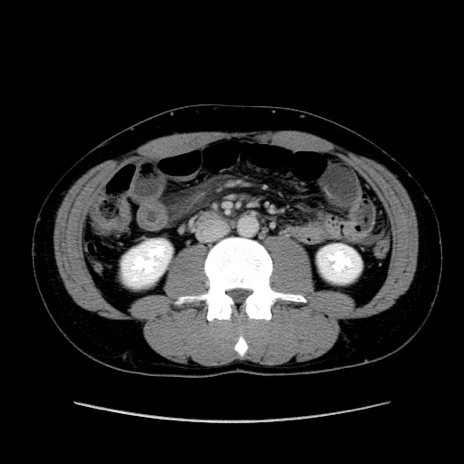

症例36(横断像)

【症例】20歳代 男性

【主訴】心窩部痛

【現病歴】今朝より上腹部痛あり。一旦軽快していたが再度出現したため救急要請。昨日夕に白身の魚を含む刺身を食べた。

【身体所見】BP 136/89mmHg、HR 74/min、BT 37.0℃、腹部:膨満、軟、心窩部に圧痛あり。反跳痛なし、筋性防御なし、腸雑音やや亢進あり。

【データ】WBC 17700、CRP 0.48